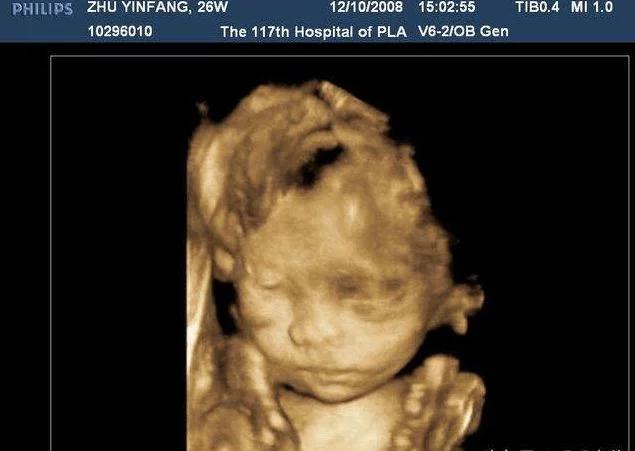

42天时去做第一次b超,就发现了有一点不对的地方,就是孕囊在左宫角那里,也许很多人,还不太了解,就是还没有到最里面,宝宝就在那里扎根了,如果乐观长长就进去了,如果不乐观,医生说就证明自己怀孕过。当然医生也不能说的那么绝对,就说明天再来一次,有专家来,再给看看。谁知这一来二去做了4次b超,让本来担心的小小,越来越担心了,心情也不再好了,这几天就哭了好几回,医生说先回家观察,只要不出血,就没有什么问题,再大一点再来观察,最主要的就是心情了。